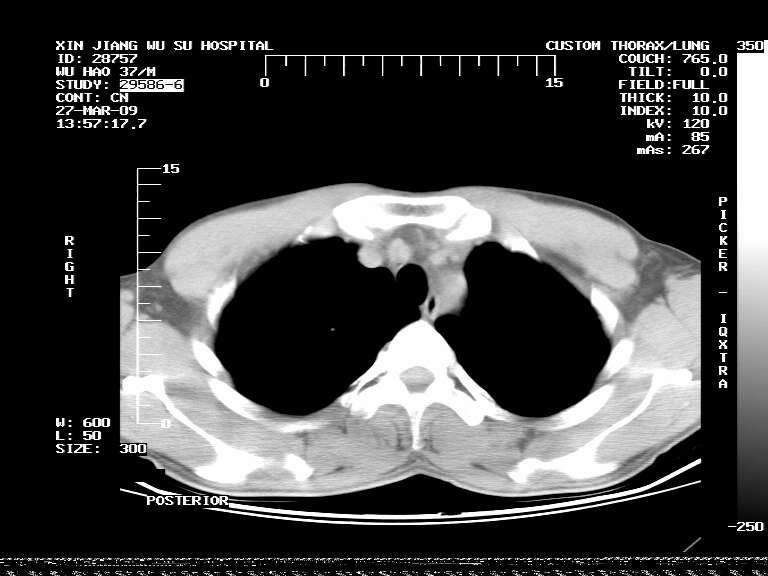

男,37岁,体检胸透发现阴影。

患者体检发现 无症状 左肺下叶占位,边缘模糊,可见血管聚束、分叶、胸膜牵拉,增强呈不均匀性强化。 首先考虑左肺下叶周围型肺癌,建议穿刺活检。

患者体检发现 无症状 左肺下叶占位,边缘模糊,可见血管聚束、分叶、胸膜牵拉,增强呈不均匀性强化。 首先考虑左肺下叶周围型肺癌,建议穿刺活检。支持!

左肺下叶见一结节病变,边缘欠清不光滑,与胸膜粘连且胸膜局限性增厚,注药后呈环形强化,动脉期壁呈明显点环状强化,静脉期壁强化减低,中心密度低无强化,灶周无明显的卫星灶和水肿区(晕征)---考虑周围性肺癌,不除外感染性病变,建议穿刺活检。

左肺下叶大片实变影,内靠胸膜见不规则更高密度结节灶,边缘强化,相邻胸膜增厚,胸膜下脂肪线存在。考虑炎症,结核可能。